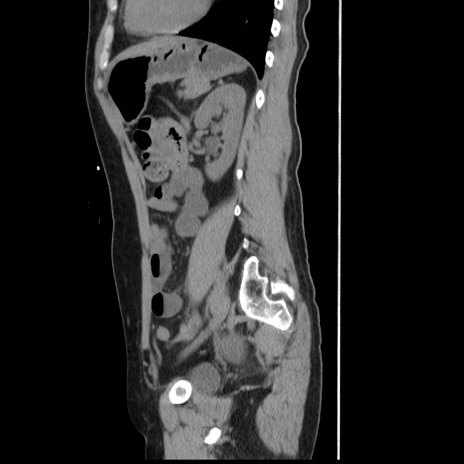

症例10(矢状断像)

【症例】 50歳代女性

【主訴】 腹痛

【現病歴】前日生レバーを食べた。今朝に排便あり。 昼前に突然発症の腹痛を生じ、当院救急外来を受診した。

【既往歴】 子宮筋腫にてで子宮全摘後

【身体所見】 意識清明、腹部:平坦、軟、下腹部やや左を中心に圧痛・反跳痛あり、筋性防御あり

【データ】WBC 7800、CRP 0.07